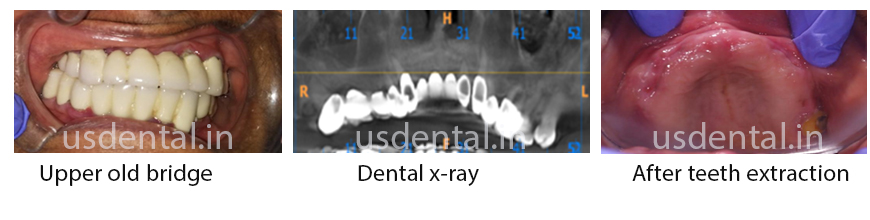

Middle aged female patient reported to US Dental clinic with a complaint of a loose upper dental bridge. Patient had this bridge before 5 years and since from that time while eating, the patient felt pain, as the dental bridge was not stable.

After clinical and radiographic evaluation, we advised the patient to go for upper all on 4 dental implants and followed by a hydride implant supported screw retained bridge.

We removed the dental bridge and extracted the teeth, waited for 1 month for soft tissue to heal around the sockets. Cone Beam CT Scan for upper jaw was done and implant planning was completed virtually. After verifying digital planning, 3D printed template was used to place 4 implants in the upper jaw utilizing principles of all on four implants. Implant supported screw retained temporary prosthesis was delivered within 72 hours after the surgery. Final screw retained ceramic bridge was fabricated 3 months after the healing time had elapsed.